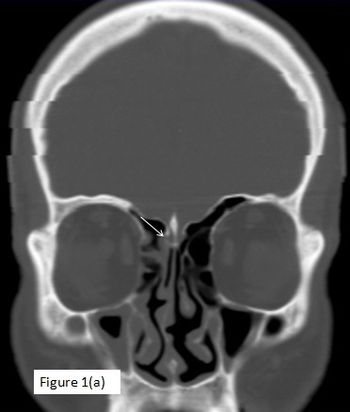

A 42-year-old male with complaints of headache and clear watery discharge from right nostril which increased on leaning forward for 15 days.